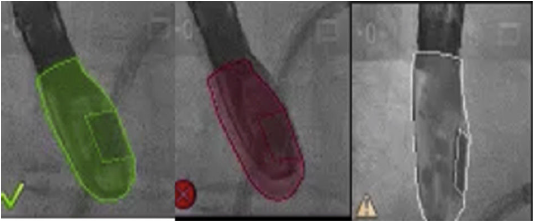

Una vez se da esta fusión, el sistema genera una imagen compuesta que sigue la rotación del brazo del fluoroscopio a discreción del cardiólogo intervencionista. La pantalla dedicada al intervencionista ofrece la posibilidad de cuatro imágenes en simultánea con diferentes funciones. En la primera, las capturas obtenidas por la ecocardiografía transesofágica 2D/3D están a cargo exclusivamente del ecocardiografista; en la segunda la visión del fluoroscopio depende de la angulación del gantry (en esta imagen se debe ubicar la sonda centrada el máximo posible en el campo visual teniendo en cuenta que a partir de allí se obtiene la sincronización del registro). La confirmación de la ubicación del co-registro de la sonda se puede ver representada de dos maneras: color verde si es adecuada o rojo si no lo es (fig. 4); el tercer cuadrante está dedicado a la imagen fusionada (el flujo del haz del transductor está graficado sobre la imagen en la cual todo cambio de posición, angulación o rotación de la sonda inmediatamente es registrado y actualizado en la fluoroscopia); por último, el cuarto cuadrante se encuentra libre para visualizar la imagen de referencia a discreción de los operadores.

Figura 4 Registro de la sonda transesofágica en el extremo de la pantalla del fluoroscopio (verde: registro adecuado, rojo: pérdida del registro, blanco: se desconoce el registro por inactividad).